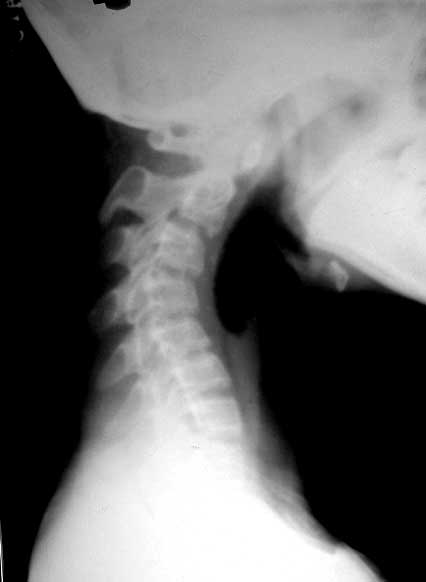

f/20y,在南方打工,电子车间作业,一坐就是五六个小时,现颈部痛。

很遗憾,只照了个侧位。

反屈如此厉害

那就是职业病引起的生理曲度消失

厉害!这么严重的颈椎反弓。[emb14]

颈椎极度后突畸形。难道每天坐五、六个小时就会出现这种改变吗?不知楼主是从哪里转贴过来的,最后的诊断是什么?

看侧位片下颌部下垂,肯定是头颈肌肉僵硬,病根还在颈部软组织。

颈椎反弓如此厉害,颈椎不稳,可怕!平常应该注意坐姿和锻炼身体。

我觉得这个病人不简单是职业病问题,5小时工作不至于此吧!不是我不同情劳动者,而是有蹊跷!首先肯定单个椎体形态还可以,可是测量好像有发育性椎管狭窄,即便如此也不至于此呀.另外只是颈痛是不存在手术干预条件的,希望患者改变习惯,更好维护自身健康!总觉得不对劲,吻合度差太多!

c23c34椎小关节不稳,需保护一下

这么严重的颈椎反弓

严重的颈椎反弓